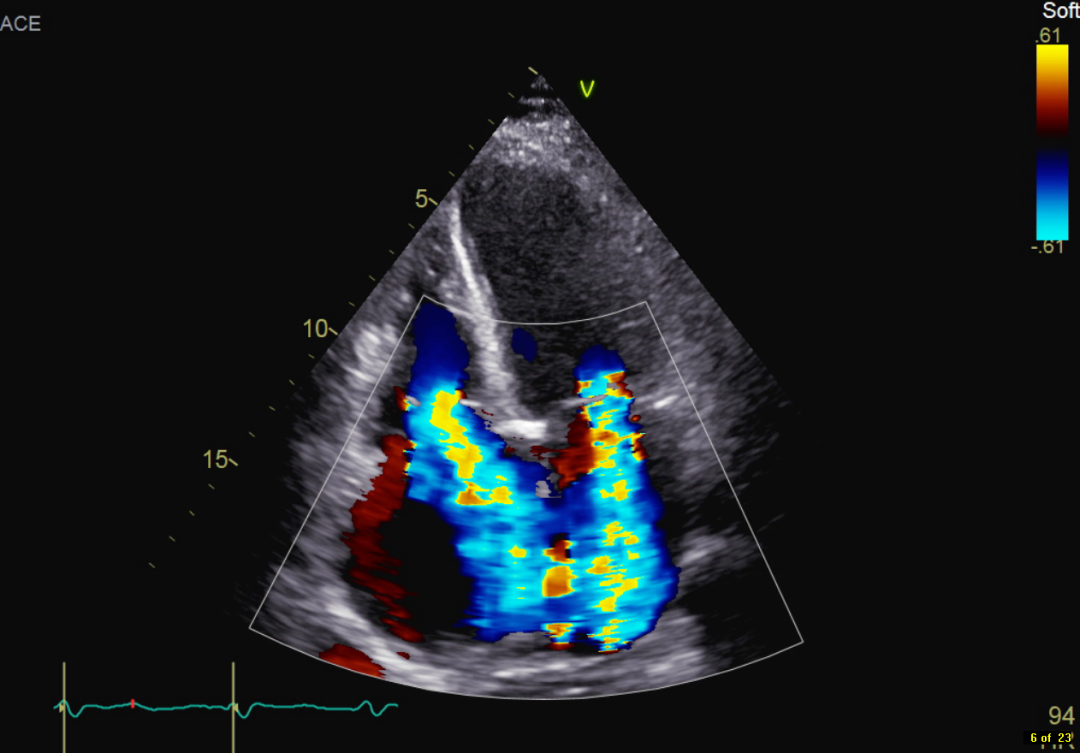

患者自述于其他医院诊断为扩张型心肌病,为进一步确认病情,吉心影像科医生为于女士进行了细致的检查。患者心电图结果显示心律失常,心房颤动,心脏彩超结果显示全心增大,二尖瓣回声增强增厚,瓣叶开放略受限,瓣叶关闭对合不良,三尖瓣开放幅度正常,关闭对合不良,左室及右室运动幅度减低。心脏超声结果显示二尖瓣关闭不全、三尖瓣关闭不全、左室收缩及舒张功能减低,右室收缩及舒张功能减低。

术前彩超影像